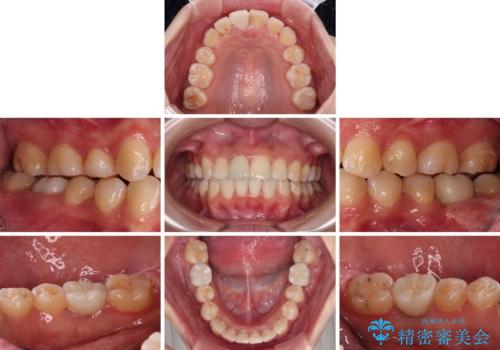

虫歯と抜いたままの奥歯とデコボコの前歯 総合歯科治療

- 放置した虫歯や抜いたままの奥歯、前歯のデコボコを気にして来院された患者様です。

口元の突出感は少なく、下顎の叢生は軽微なものであったので、叢生の強い上顎左右の小臼歯を1本ずつ抜歯し、ワイヤー装置にて矯正治療を行うこととしました。

矯正治療を行う前に、根管治療の必要な上顎前歯と下顎大臼歯の根管治療を行い、矯正治療の途中で下顎の欠損部にインプラント埋入することとし、矯正治療後に補綴治療を行うこととしました。